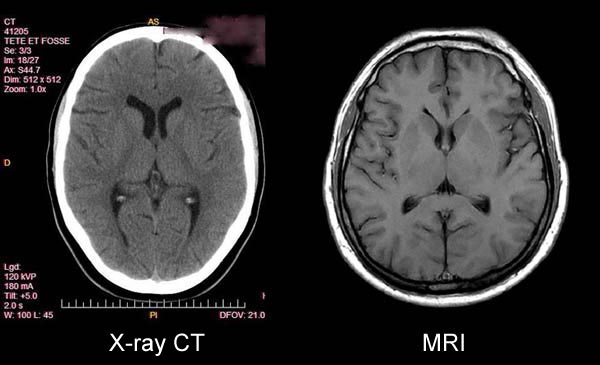

(pixels-Fig 14c) Accordingly the power to visualize DETAIL in the body's CRITICAL SOFT TISSUE VITAL ORGANS (e.g. Brain, Heart, Muscles, Kidney, Liver, Spleen, Pancreas, Intestines) therefore RESTS ENTIRELY on the power of the imaging technology to generate the PIXEL CONTRAST needed to visualize IMAGE DETAIL in the body's vital tissues. The existing x-ray technology for visualizing IMAGE DETAIL in the body's CRITICAL VITAL ORGANS had been severely lacking in its power to generate the PIXEL CONTRAST needed to visualize IMAGE DETAIL in the body's CRITICAL VITAL SOFT-TISSUE ORGANS Dr. Damadian's

Damadian's discovery of the "signal that makes the image" provided anotherVITAL DISCOVERY.It provided,FOR THE FIRST TIME IN MEDICAL HISTORY,the power to achieve clear visualization of the body'sVITAL ORGANS.Prior to the

advent of MRI, medical imaging from its x-ray inception

in 1895 was uniquely deficient in its ability to achieve

satisfactory (and necessary)

visualization of the life-sustaining organs of the

human body (Brain, Heart, Muscles,

Kidney, Liver, Spleen, Pancreas, Intestines ...).

X-ray technology was significantly limited in its

QUESTION:

What did MRI bring to medical

imaging that had been lacking

for the better part of a century

(W. Roentgen X-ray 1895) ?

ANSWER:The power to visualize

Unprecedented

Medical Image Detail in a medical image

for the first time in medical history.

(Fig 7 & 8)

QUESTION: What did Dr.

Damadian's DISCOVERY

provide to medical images that SURMOUNTED

the inability of existing medical imaging technology

(x-ray) to visualize DETAIL

in medical images?

ANSWER: PIXEL CONTRAST

QUESTION: What delivered

the

PIXEL

CONTRAST ?

ANSWER: T1 and T2.

The differences in the tissue

NMR relaxation times (T1 and T2) of the body's

healthy tissues (131%),

DISCOVERED

by Dr. Damadian (Tables 1 & 2, Fig 6), provided

the signal amplitude differences that generate the

pronounced brightness DIFFERENCES

of the MRI image pixels and produce a 131%

PIXEL CONTRAST for the visualization of ANATOMIC

DETAIL in MRI medical images that had been

limited to a maximum PIXEL

CONTRAST of 4% for visualizing anatomic

detail by x-ray.